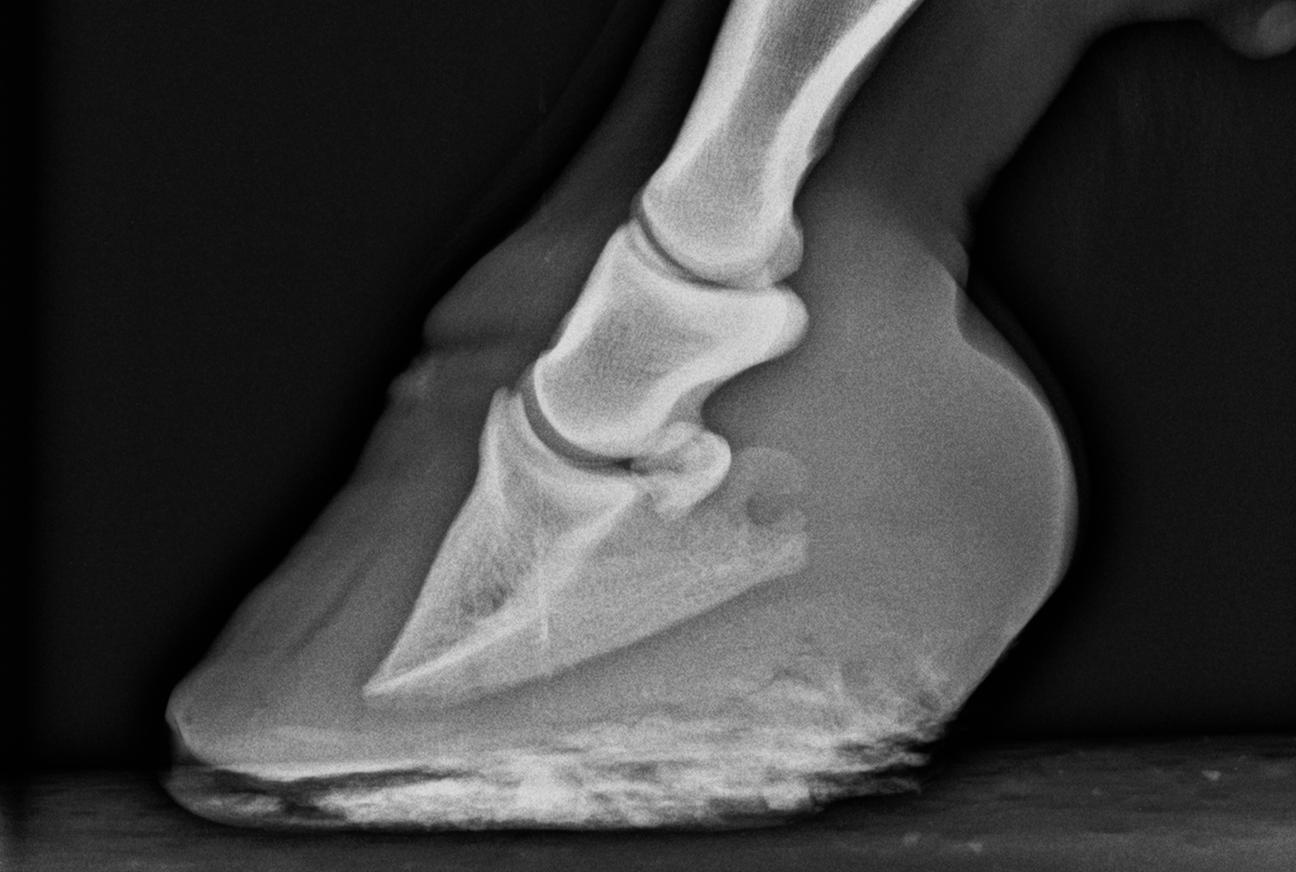

Röntgenundersökningar

Röntgenundersökningar utföres i samband med hältundersökningar, besiktningar och vid sk friröntgen av unga hästar. Röntgen av halskotpelare och rygg vid ryggproblem samt av skalle och tandrötter vid misstanke om bihålesjukdom respektive tandproblem. Självklart kan det bli aktuellt att även röntga en sårskada eller en märklig knöl på ett ben.